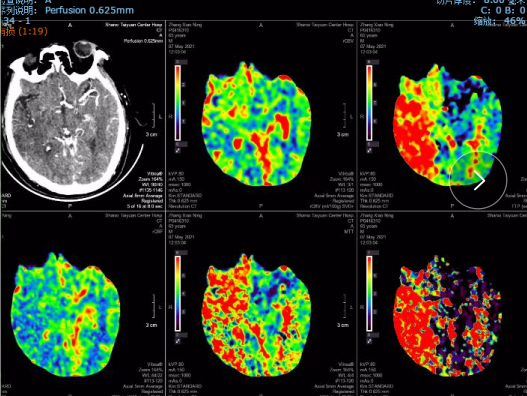

CTP:

右侧大脑半球均存在不同程度的低灌注区域。

此患者临床症状非急性右侧大脑中动脉闭塞患者,有左侧肢体偏瘫、语言不流利等较重的临床症状,NIHSS评分15分(意识提问2+凝视2+构音障碍1+面瘫1+偏瘫8+感觉障碍1),mRs评分4分,生活不能自理。但是头颅CT表现却不是整个右侧半球的大面积梗死,MRA和CTA均提示右侧大脑中动脉M1段闭塞,脑灌注提示右侧半球明显低灌注。提示虽然右侧大脑中动脉闭塞,但是其支配区域仍然有一定体积的处于低灌注目前尚未完全坏死的脑组织,符合血管内再通手术指征。